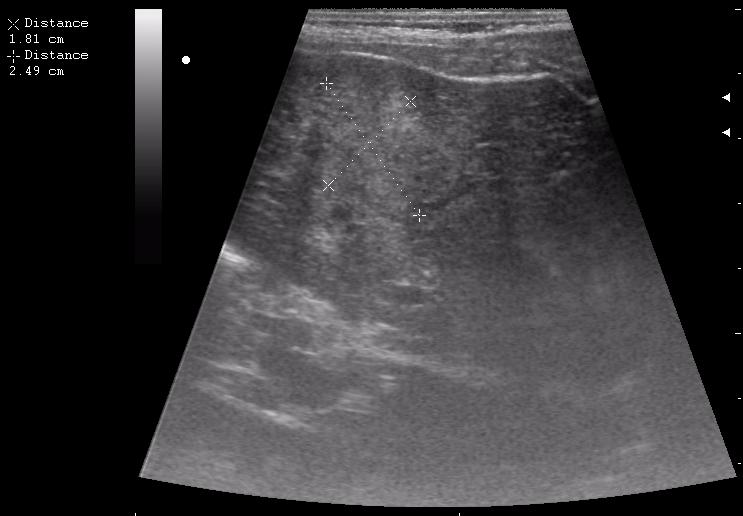

наезд большой черной Прады на маленькую (13кг) 5-летнюю девочку.

получает Медаксон, рабочая версия - изменение желчного пузыря вследствии травмы (шепотом - рекомендация хирургу сменить антибиотик)